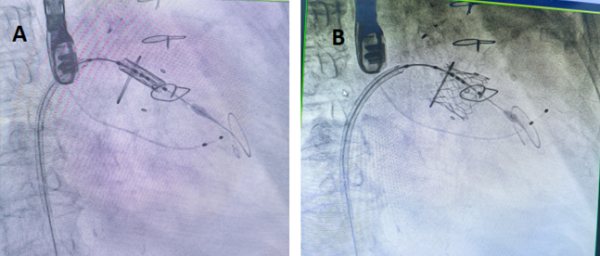

手术过程:A.瓣膜定位;B.瓣膜释放;

手术当天,团队为刘英芳开启了 “心门修复” 之旅。由右侧股静脉入路,使用房间隔穿刺器穿刺房间隔,开通股静脉-房间隔-左心房-左心室的通路,插入导丝和鞘管建立输送轨道。房间隔处进行预扩张处理,将预装好瓣膜的输送系统沿导丝推送至二尖瓣瓣环位置,在经食道超声实时指导下进行瓣膜的精准定位。快速起搏,待血压降至50mmHg以下充盈球囊实现瓣膜的释放。